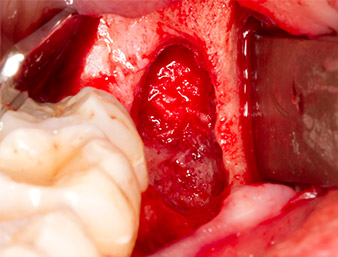

A continuación, se utilizó el accesorio P1 para retirar de una pieza el resto radicular de aproximadamente seis milímetros de longitud (figura 11).

El tejido inflamatorio periapical se retiró también con sumo cuidado utilizando un excavador manual. La figura 12 muestra el alvéolo vacío con el nervio alveolar inferior expuesto.

radicular extraído

Imagen 11: El resto radicular extraído medía más de 6 milímetros.

Nervus alveolaris inferior

Imagen 12: En la profundidad del alvéolo se distingue el nervio alveolar inferior.